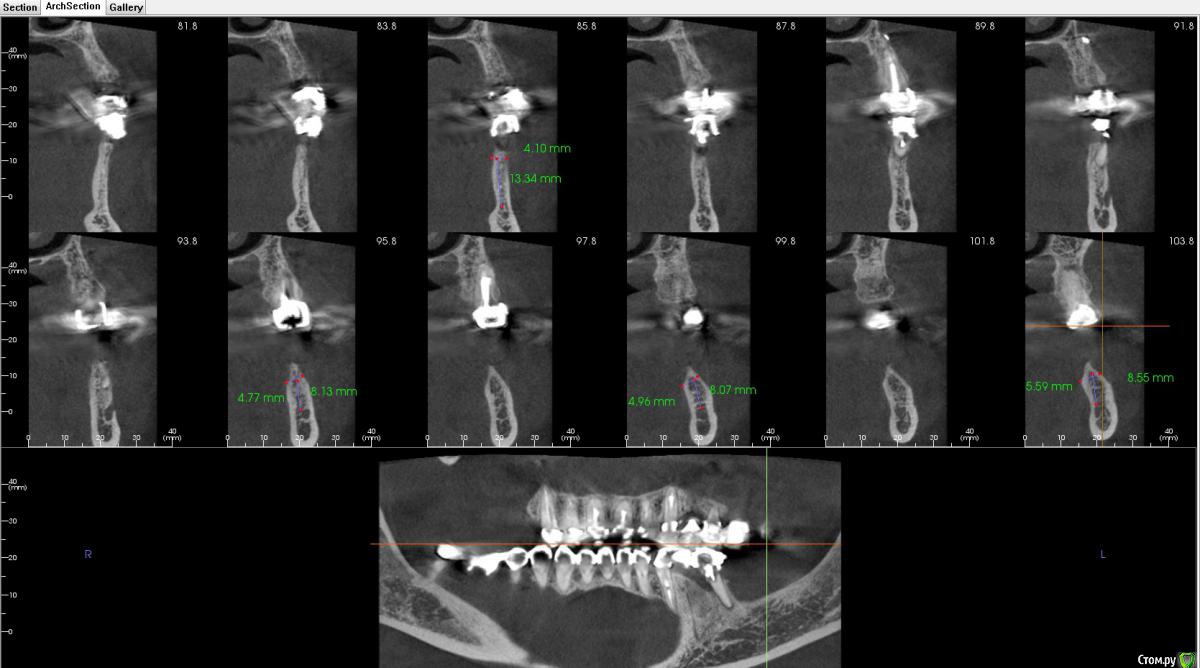

Bier Опубликовано 2 ноября, 2018 Поделиться Опубликовано 2 ноября, 2018 я честно говоря не понял в каком месте среза сколько кости. Где-то кости достаточно для установки имплантата без пластики, где-то нет. Ссылка на комментарий

Bier Опубликовано 3 ноября, 2018 Поделиться Опубликовано 3 ноября, 2018 блин, Камранчик, я вообще не понимаю в какую зону ты хочешь ставить и как твою нарезку прикрепить к панораме, которая ниже. Никакой системы координат нет.Короче там, где гребень 4.7 - можно крутить и не делать пластик. Ссылка на комментарий

Дмитрий Л. Опубликовано 3 ноября, 2018 Поделиться Опубликовано 3 ноября, 2018 Короче там, где гребень 4.7 - можно крутить и не делать пластик.Провокативно.3,5 в моляр? Ссылка на комментарий

Irouil Опубликовано 3 ноября, 2018 Поделиться Опубликовано 3 ноября, 2018 не совсем понял твою мыслю))После редукции до ширины гребня 4 мм крутить 3.5 ориентируясь на язычную стенку, если торчит только краешек 1 мм вестибулярно то бугром 1 Ссылка на комментарий

Bier Опубликовано 4 ноября, 2018 Поделиться Опубликовано 4 ноября, 2018 После редукции до ширины гребня 4 мм крутить 3.5 ориентируясь на язычную стенку, если торчит только краешек 1 мм вестибулярно то бугромредуцировать не надо, надо заглублять. Апроксимальные костные пики обеспечат стабильность мягких тканей. 2 Ссылка на комментарий

Bier Опубликовано 4 ноября, 2018 Поделиться Опубликовано 4 ноября, 2018 Язычно много не будет?редукцию надо проводить ровно под абатмент будущий. 1 Ссылка на комментарий